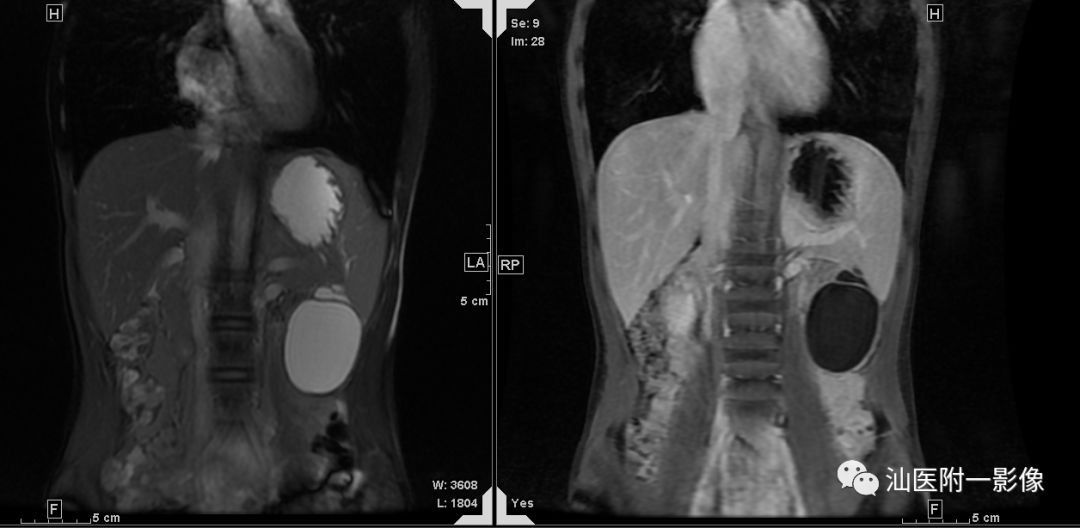

·男,15岁,上腹痛3天,加重半天

·3天前无明显诱因出现上腹痛,呈持续性痛。半天前症状突然加重。查体:全腹部腹肌紧张,左上腹部压痛及反跳痛明显。

·外院B超:左上腹囊性包块,考虑胰腺假性囊肿,未排其它

病例二 胰腺假性囊肿